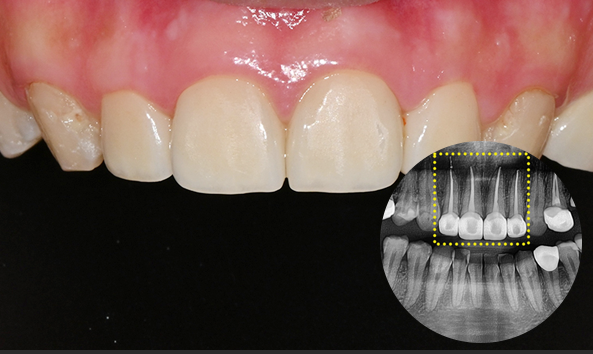

세라믹 인레이 (e.max)

자연치아와 유사한 색감·투명도, 심미성과 강도 우수